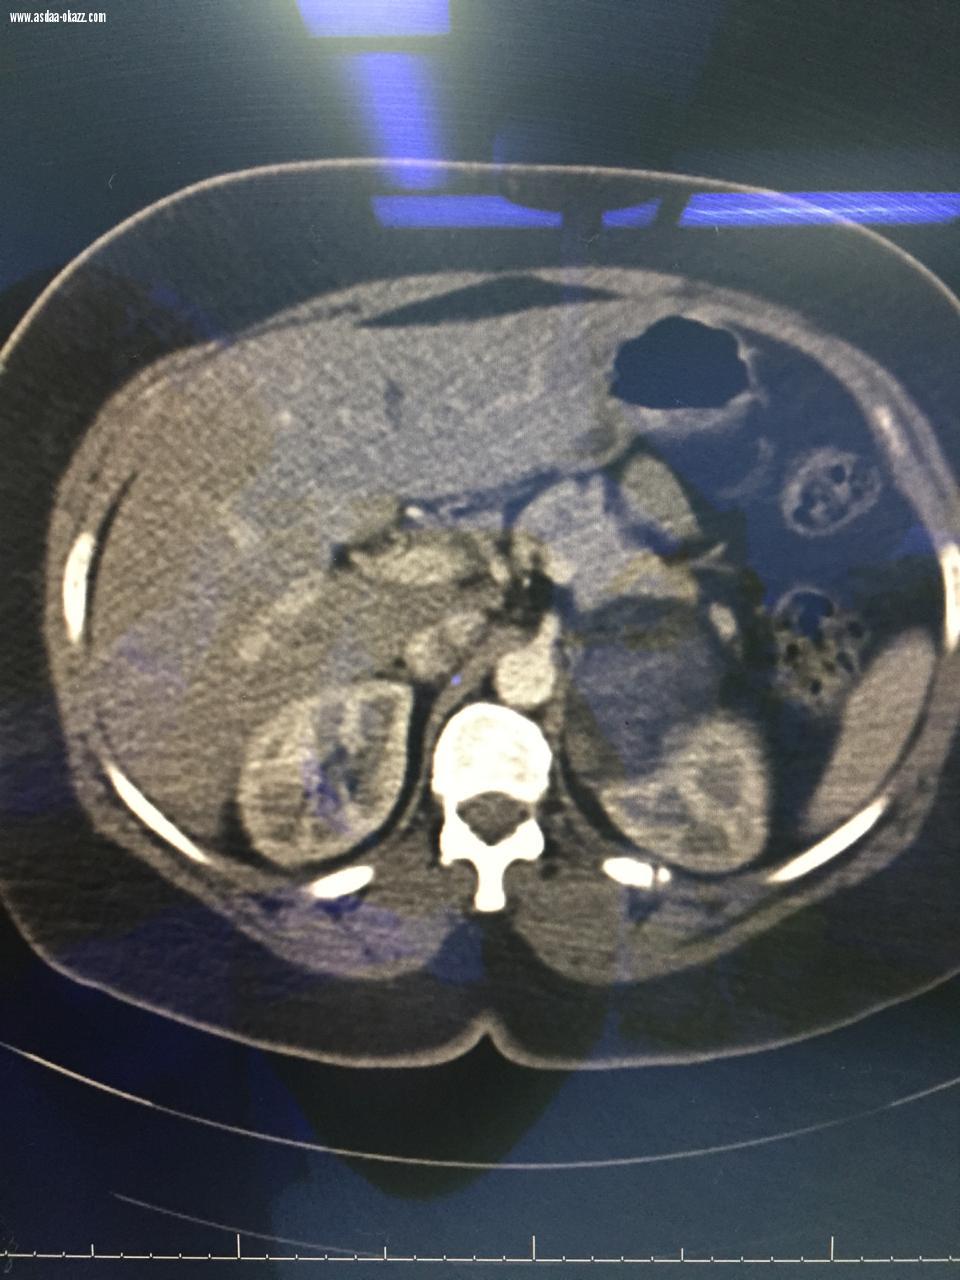

أنهى فريق جراحي بمستشفى الملك عبد العزيز بجدة معاناة مواطنة في الخمسينات من عمرها ، إثر إكتشاف ورم حميد غير نشط في الغده الكظرية اليسرى ، و جاء إكتشاف الورم بالصدفة و ذلك بعد معاينة المريضة نتيجة إصابتها في حادث مروري منذ سنتين .   و قد تقرر إجراء عملية بالمنظار أستغرقت ثلاث ساعات ، تكللت ولله الحمد بالنجاح ، حيث بلغ حجم الورم تقريباً ٨x٦x٦ سم ، و تعد هذه الحالة من الحالات النادرة و الدقيقة ، إذ أن نسبة إكتشاف أورام الغدد الكظرية بالصدفة أثناء إجراء الأشعة التشخيصية للبطن تقريباً ٥ ٪ ، و أجرى العملية الدكتور بدر عبداللطيف الدريس استشاري جراحة أورام الثدي و الغدد الصماء ، و الدكتور أيمن زمريق استشاري جراحة الجهاز الهضمي .